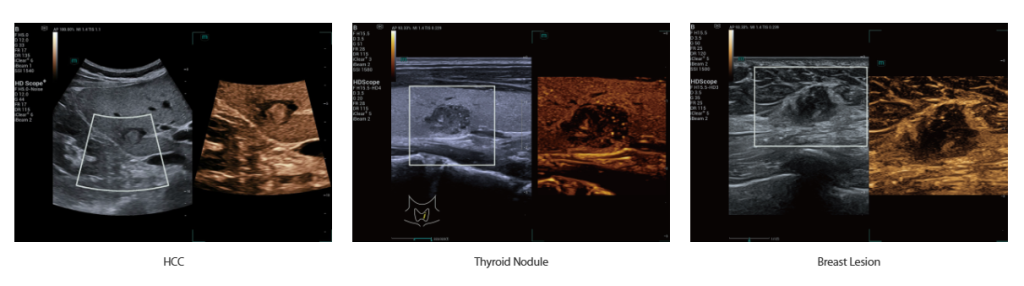

Ultra Micro Angiography (UMA)

Обновленная технология UMA позволяет с высокой чувствительностью фиксировать минимальный низкоскоростной кровоток, обеспечивая при этом высокое пространственное разрешение и эффективный контроль артефактов движения. Эти усовершенствования значительно повышают диагностическую точность при оценке кровоснабжения органов и исследовании новообразований.

-

Высокая чувствительность

-

Высокое разрешение

-

Эффективная фильтрация артефактов движения

-

Пересаженная почка

-

Папиллома кожи